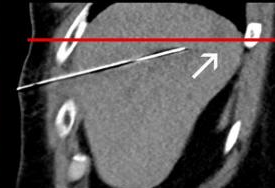

联合骨组织/软组织活检

|

椎体破坏 |

局麻 |

14G骨入路 |

16G TruCut 活检针:Osteolytic bone metastasis from urothel carcinoma |